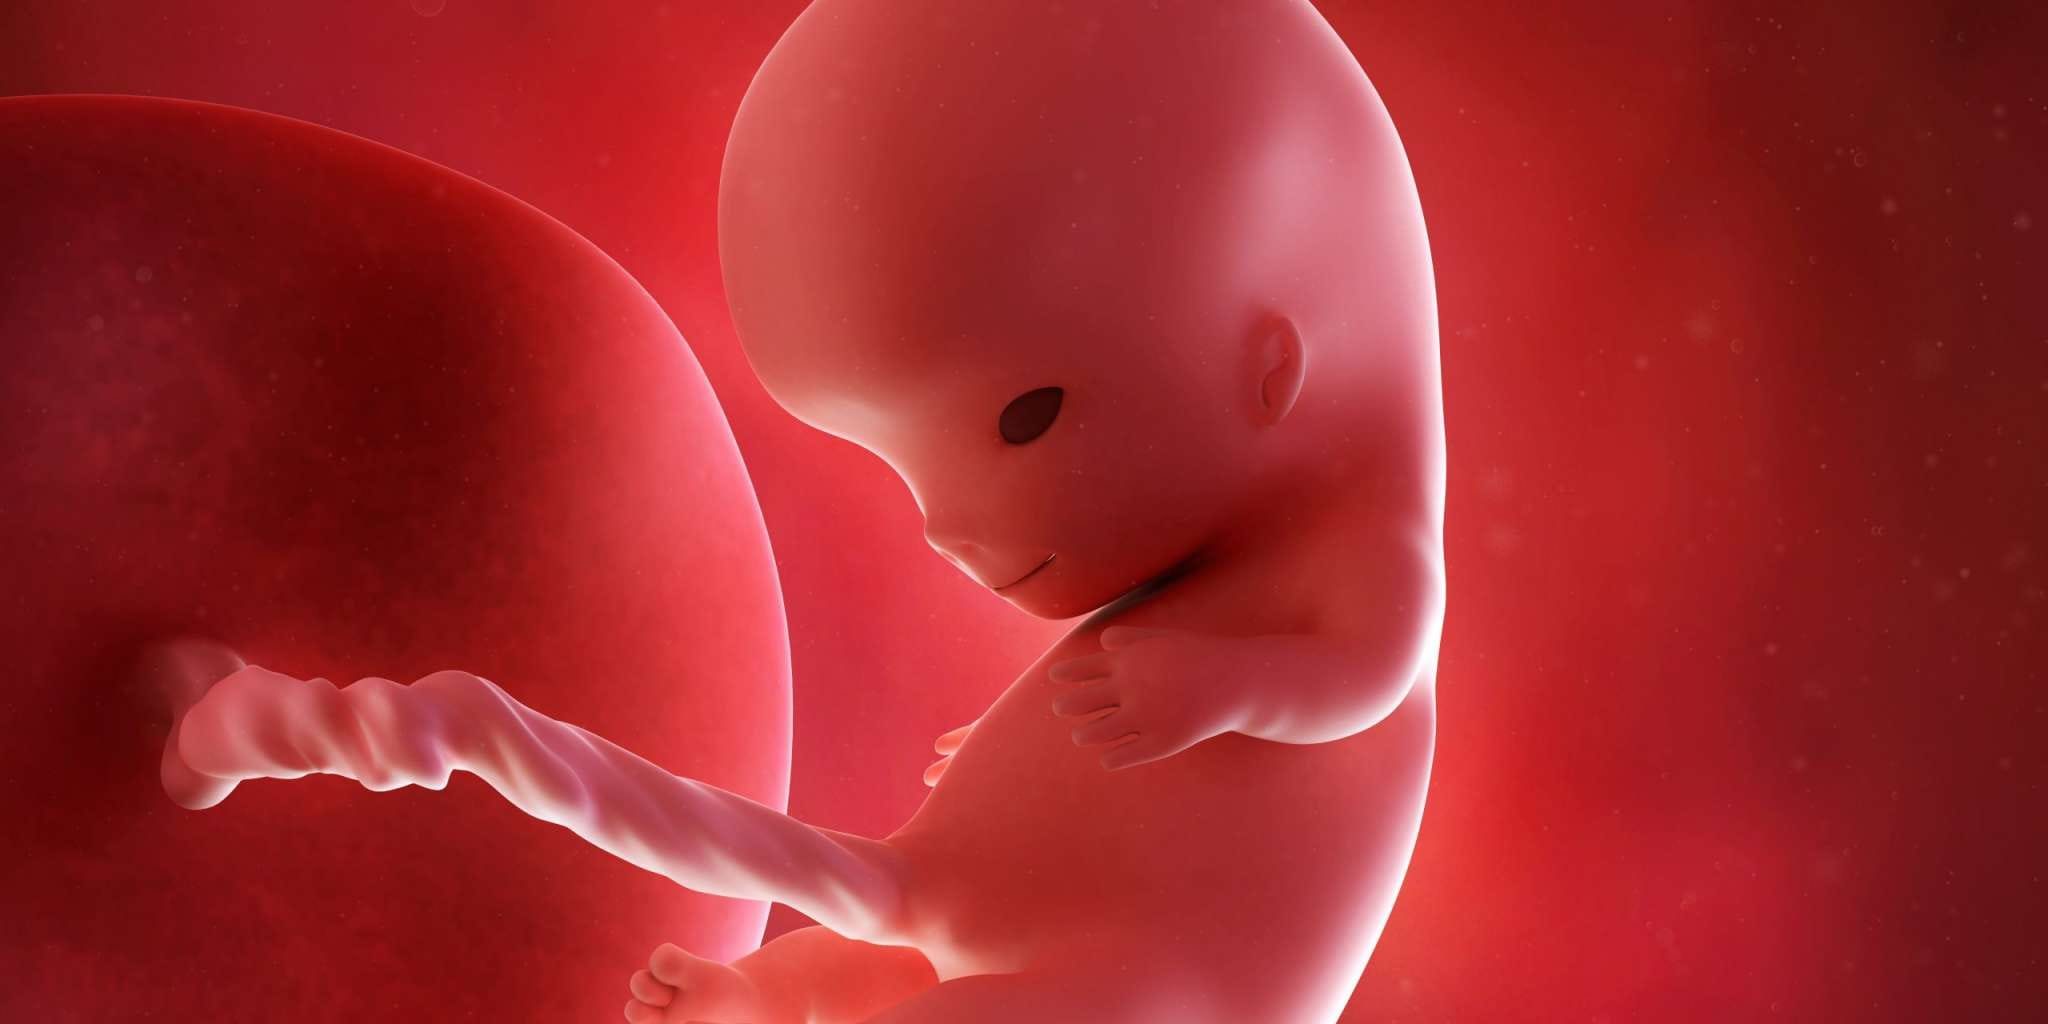

- hafta, hamileliğin 3. ayına giriş yapılan ve fetüsün hızlı bir gelişim sürecine girdiği bir dönemdir. Bu hafta itibariyle embriyo artık “fetüs” olarak adlandırılır. Çünkü gelişimi artık organ oluşumundan fonksiyon kazanmaya doğru evrilmiştir.

- Tüm organ sistemleri artık temel olarak oluşmuştur. Bundan sonraki haftalarda bu sistemler gelişip olgunlaşacaktır.

- Beyin gelişimi hızla devam eder. Beyin, vücut oranlarına göre büyük görünebilir.

- Yüz hatları belirginleşmeye başlar: Gözler birbirine yaklaşır, kulaklar yerini bulur.

- Parmaklar artık ayrı ayrı seçilebilir; parmak arası perdeler kaybolmuştur.

- Tırnak yatakları oluşmaya başlar.

- Kollar ve bacaklar uzar, dirsekler ve dizler netleşir.

- İç organlar (karaciğer, bağırsaklar, böbrekler) işlevsel duruma geçmeye başlar.

- İlkel diş tomurcukları oluşmuştur.

- Omurga daha belirgin hale gelir.